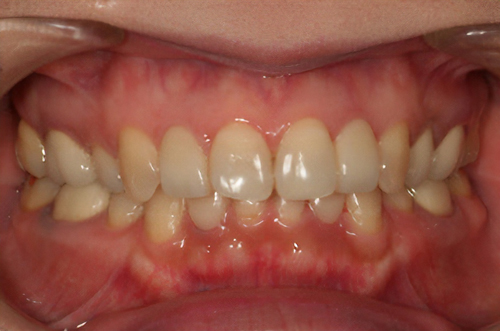

黒ずんだ歯肉の色をお薬で、キレイなピンク色の歯肉にします。

塗り薬の麻酔と薬液だけで10分程度、2回の治療でキレイなピンク色に。-

術前

術後

※ガムピーリングの効果には個人差があります。

- > 一時的に沁みることがある。

- > 個人差がある。

- > 色素が深い場合は変化しない部位が残ることがある。

副作用:一時的に歯肉が沁みることがある。1週間程度歯肉は白くなる。